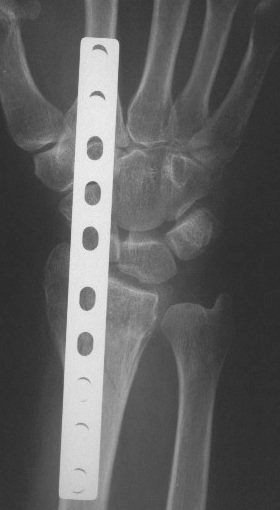

Clinical Example: Distraction plate fixation distal radius fracture

distal radius fracture

distraction plate